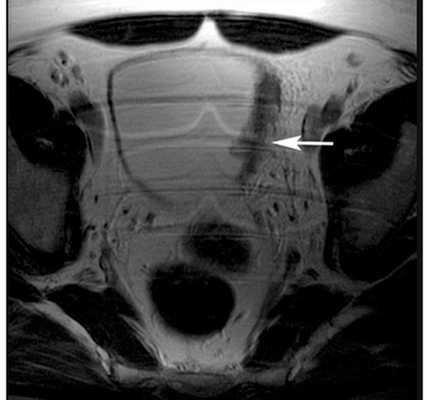

Магнитно-резонансная томография

Как и компьютерная томография, магнитно-резонансная томография обеспечивает получение детализированных изображений тканей и органов. При этом обследовании используются радиоволны и магнитные поля вместо рентгеновских лучей. Энергия радиоволн поглощается тканями организма, а компьютер преобразовывает информацию и отображает ее в виде рисунка. В процессе исследования в вену также может вводиться контрастное вещество для получения более четких изображений и деталей.

Рисунок. Рак мочевого пузыря на стадии T2b, с инвазией в мышечный слой.

Магнитно-резонансная томография особенно полезна в определении того, насколько далеко опухоль распространилась за пределы мочевого пузыря.